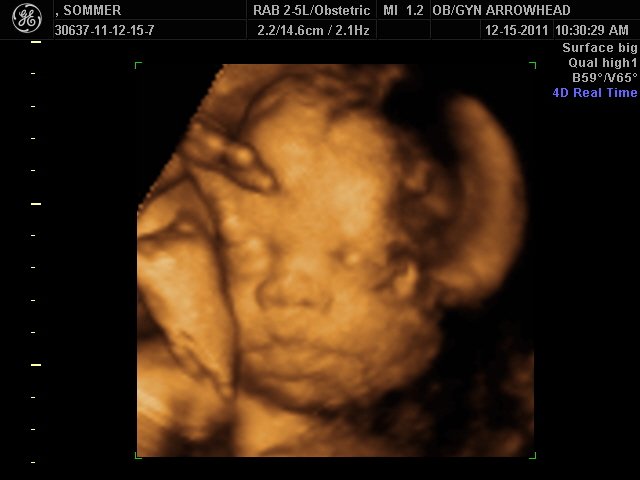

We offer complimentary 3D/4D Ultrasounds to all our OB patients around 30 weeks! The following photos are some examples of our work, shown with permission from our patients.